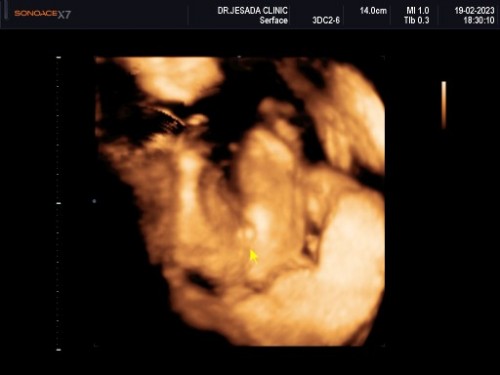

รูปนี้ เเม่ๆว่าเหมือนไข่ มั้ยคะ555

หมอว่าเป็นเเคม น้องเป็นผู้หญิง เเต่เเม่มองเป็นไข่55555 มีเเม่ๆคนไหน ซาวเพศเเล้วเจอแบบนี้บ้างมั้ยคะ หญิง หรือ ชาย #20week

แคปมาจากวีดีโอค่ะ เป็นเเบบนี้

ไข่ค่ะ บ้านนี้ก็ไข่ น้องหนีบไข่มันเลยออกมาเป็นนั้น😂

มันไม่ค่อยชัดเนาะ น้องอาจจะหนีบจู๋ไว้ก็ได้ค่ะ😆

555คิดเหมือนคุณเเม่เลยค่ะ ถามหมอว่ากี่% หมอตอบว่า ไม่ทราบ ตอบเท่าที่เห็น เเม่ งงเลย55

ใช่มั้ยคะเเม่ อยากให้เป็นเเคมจริงๆ เเต่ทางบ้านเห็น ว่าเป็นไข่ เลยไม่มั่นใจเลย